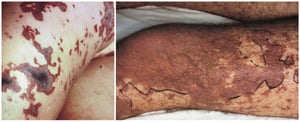

La meningococcemia fulminante provoca inizialmente petecchie, che diventano confluenti e progrediscono rapidamente verso le ecchimosi.

Le petecchie sono isolate in alcune aree e coalescenti e sviluppano necrosi in altre aree (a sinistra). Si apprezza una vasta area di necrosi (a destra).

Le petecchie sono isolate in alcune aree e coalescenti e sviluppano necrosi in altre aree (a sinistra). Si apprezza un